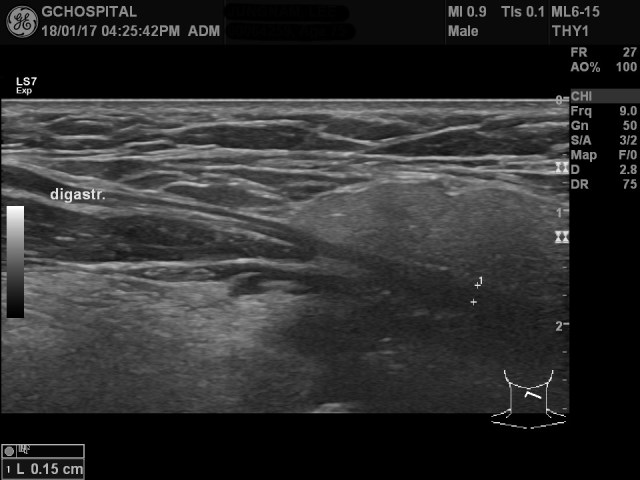

이렇게 하측방향으로 주행하는 하악이복근의 주행방향을 따라 스캔한 영상입니다. 하악이복근은 잠시동안은 더 깊게 위치해있는 하악설골근과 함께 보이다가 점점 가늘어지면서 설골 위쪽에 anterior & posterior belly를 고정시켜주는 구조물을 향해 주행하게 됩니다.

이렇게 하악 이복근의 앞쪽 근육, 즉 anterior belly는 매우 가는 힘줄로 변하면서 한번 꺽인 후에 뒷쪽 posterior belly와 연결되는데, 이렇게 앞뒤쪽 이복근을 잡아서 고정시켜주는 활차는 생각보다 설골(hyoid bone)에서 꽤 떨어져서 위쪽에 존재하며, 초음파영상에서는 위와 같이 턱밑샘(submandibular gland)의 깊은 부위에서 확인할 수 있습니다.

이렇게 anterior 및 posterior belly가 약간의 앵글을 이루면서 연결된 이후부터는 posterior belly muscle을 확인할 수 있습니다. 생각보다 깊지 않은 곳에 위치하며, 턱밑샘 뒷쪽으로 주행하는 posterior belly 근육을 확인할 수 있습니다. anterior belly에 비해 근육 자체의 두께는 더 얇은 편입니다.